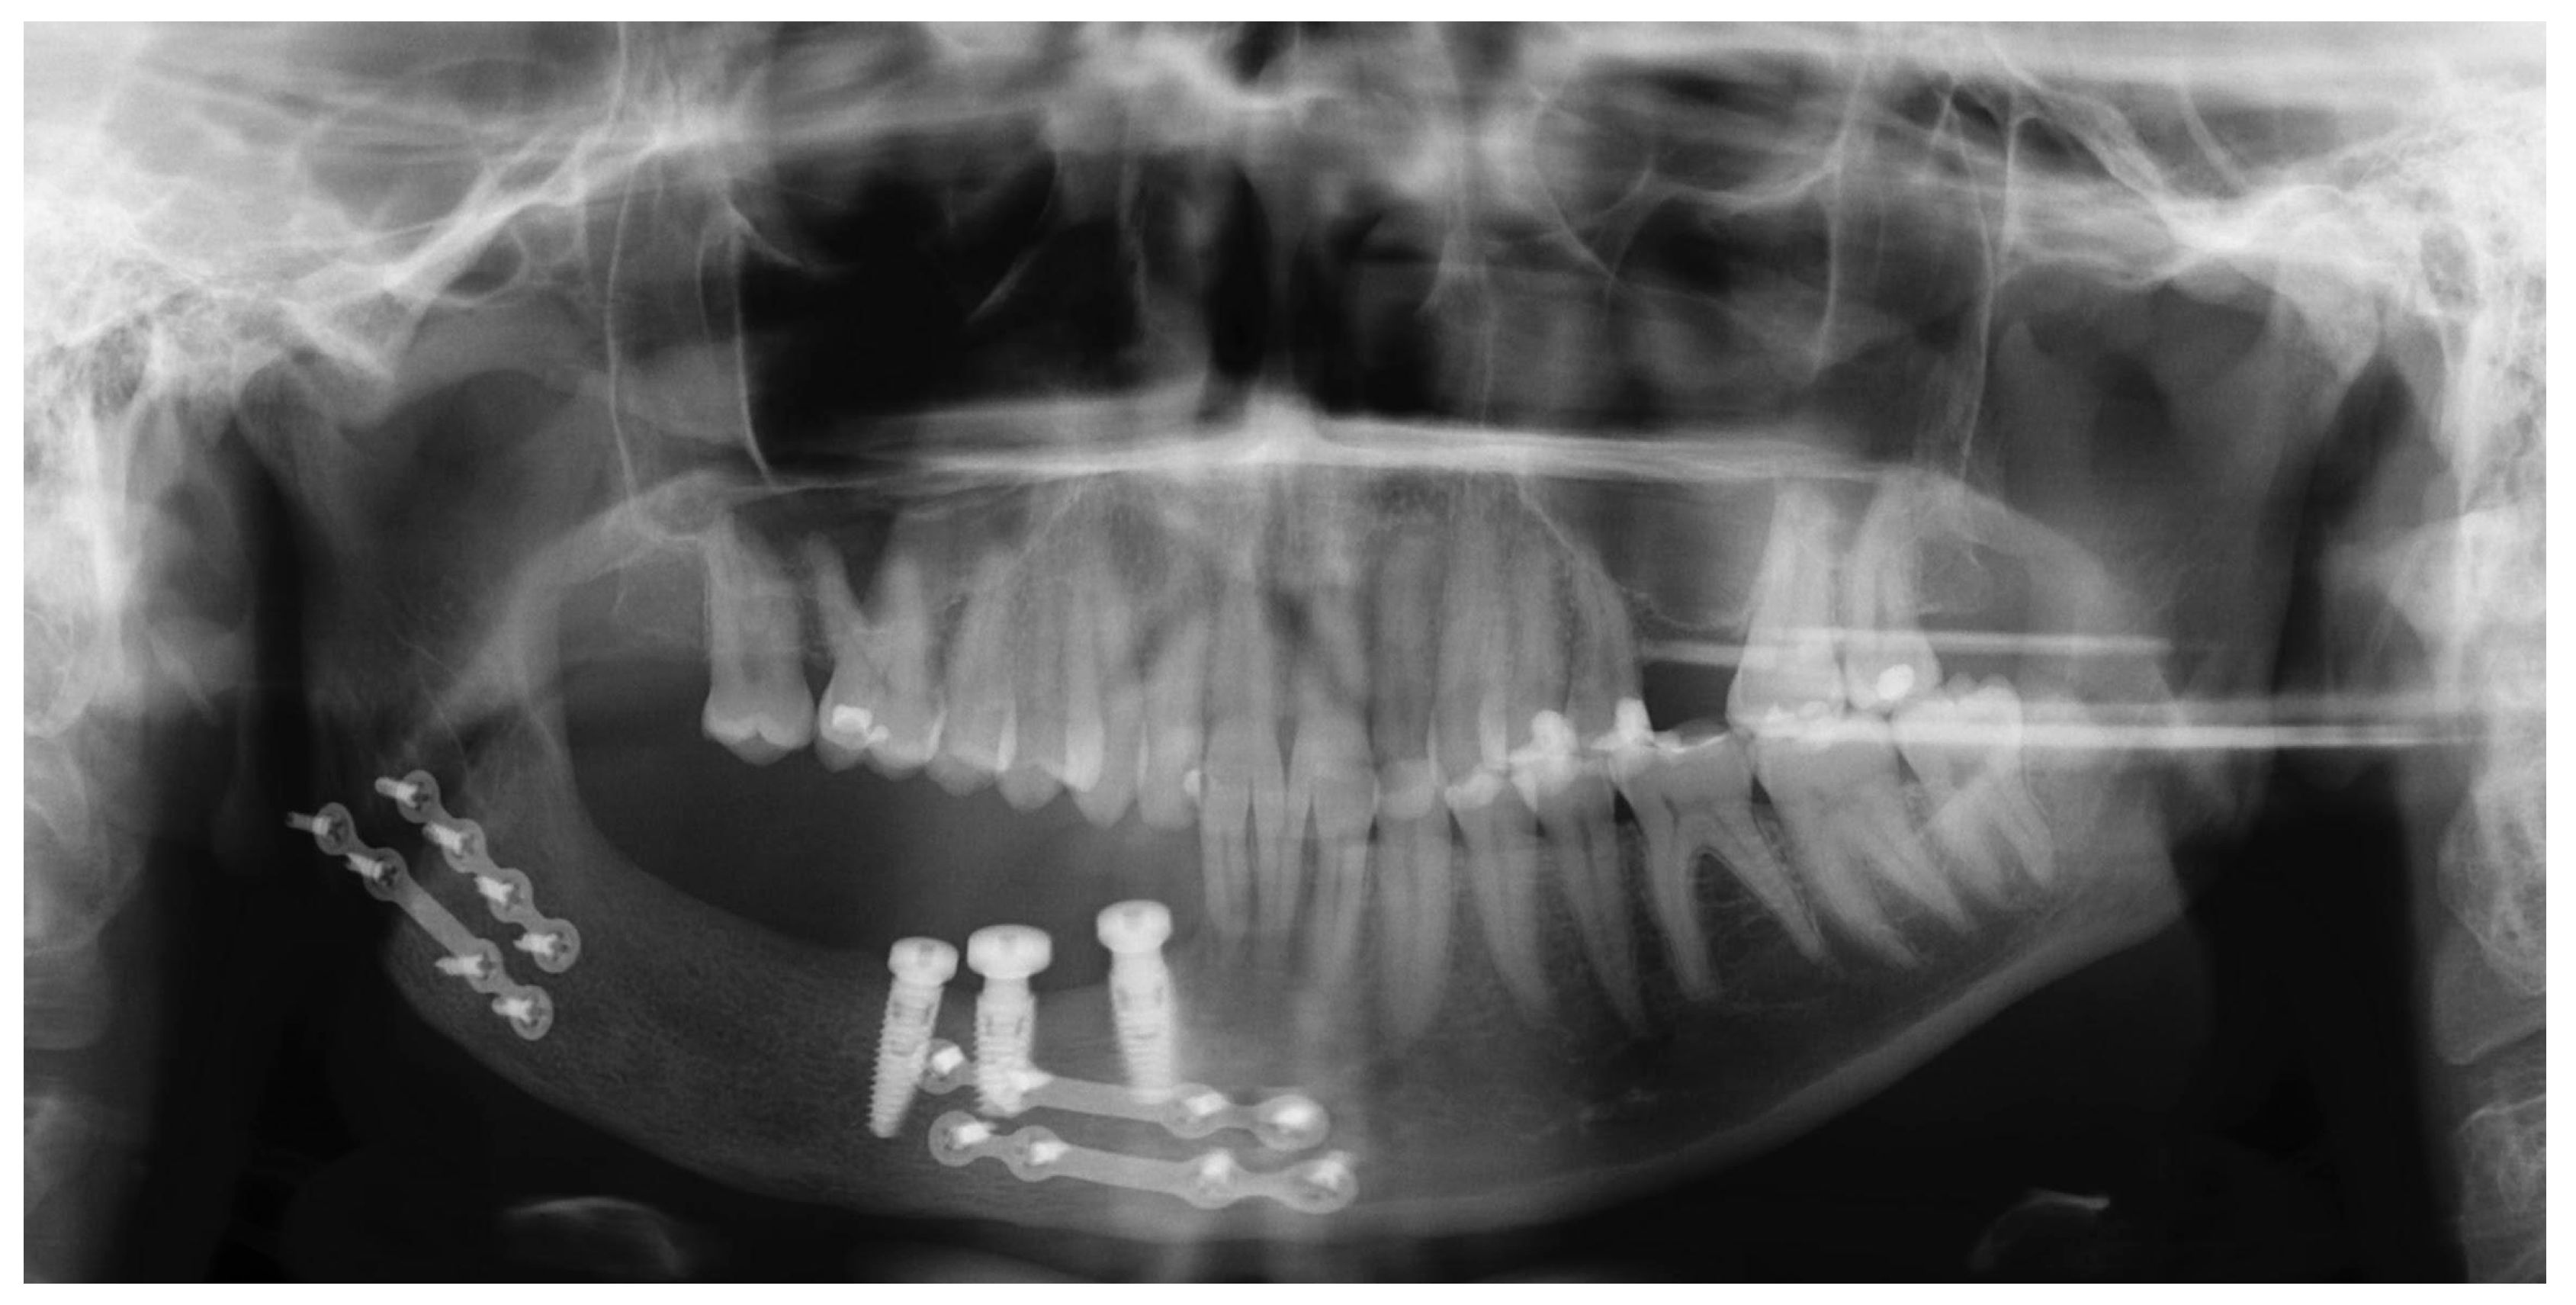

2.4. Follow-Ups

| Timing for Implants | Delay between the bone graft and implant placement: 4–6 months to ensure graft consolidation and stability. | [9,18] |